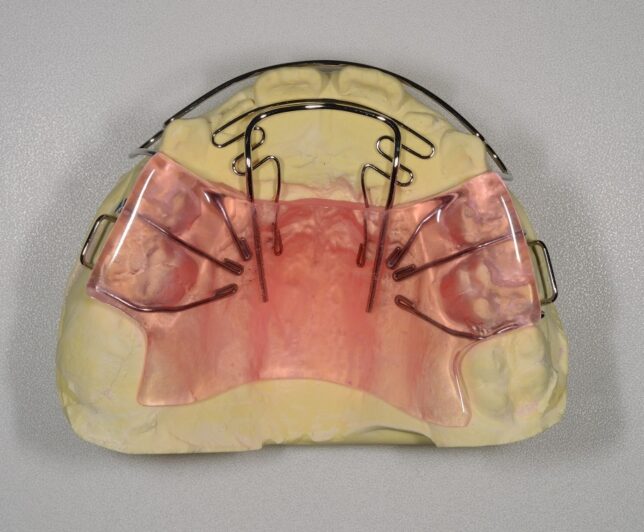

こんな場合は、下の画像のような取り外し式の矯正装置を使います。

この装置はプレオルソと違い、歯型を取って作成するので、歯型を取るというハードルはあるのですが、作ってしまえば、プレオルソより違和感は少なく、ほぼ問題なく、装着してくれます。

- 治療方法 床矯正装置